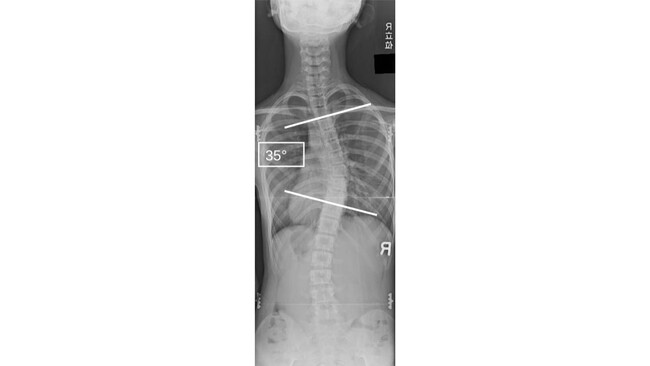

(注2)コブ角:側弯症の程度を表す角度の指標で立位や座位のレントゲンで最も傾いている椎体(脊椎骨)同士のなす角で計測します(図2)。

脊椎の正面や背後から見た際の左右へのゆがみや曲がりを脊柱側弯症(注1)といい、特に思春期に発症する原因不明のものを思春期特発性側弯症とよびます(図2)。自覚症状に乏しいことから自分自身や家族の方が気づかないことも多いため、学校検診にも組み込まれていますが、既存の方法(視診やモアレ法が有名です)では感度の問題や、検査に必ず検査者を必要とすることから頻回の検査が困難であり、適切な時期に検知できない、などの問題点が指摘されていました。一方で特発性側弯症は成長期に急速に悪化することが知られており、進行すると手術が必要になることもあるため、コブ角が25°程度を超えた時点で成長段階によっては、進行を防ぐために装具治療に代表される保存療法を開始する必要があります。こうした背景から特に治療を要するような脊柱側弯症を再現性よく、適切なタイミングで検知できるような新たなスクリーニング方法の開発が必要とされていました。